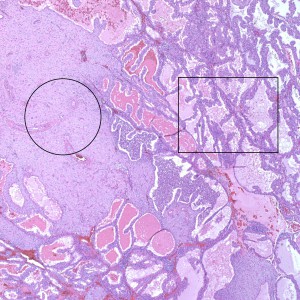

At low power, the majority of the specimen consists of decidua (square) and gestational-type endometrium (circle).